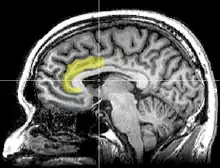

Sagittal MRI slice with highlighting indicating location of the anterior cingulate cortex.

The anterior cingulate gyrus shows increased activity when viewing conflicting stimulus.[8]:454

Brain imaging techniques including magnetic resonance imaging (MRI), functional magnetic resonance imaging (fMRI), and positron emission tomography (PET) have shown that there are two main areas in the brain that are involved in the processing of the Stroop task.[9][10] They are the anterior cingulate cortex, and the dorsolateral prefrontal cortex.[11] More specifically, while both are activated when resolving conflicts and catching errors, the dorsolateral prefrontal cortex assists in memory and other executive functions, while the anterior cingulate cortex is used to select an appropriate response and allocate attentional resources.[12]